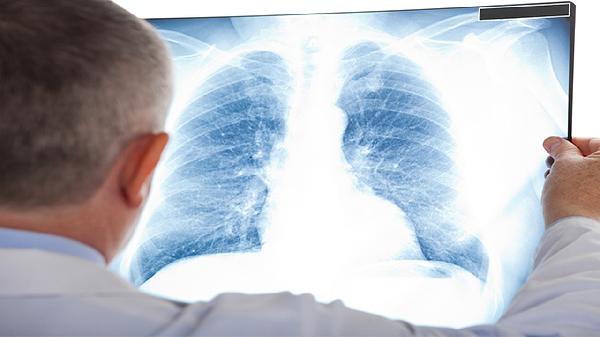

二、进行胸部影像学检查

胸部X线或CT检查是诊断肺炎的重要依据。支原体肺炎的影像学表现多样,典型特征包括肺部出现斑片状、云絮状的模糊阴影,密度较淡,边缘不清,多分布于肺下叶。部分患者可表现为间质性肺炎的改变,如肺纹理增粗、紊乱,或出现网格状、结节状阴影。影像学检查可以明确肺部炎症的范围和性质,但同样不能直接确定病原体为肺炎支原体,需要与其他类型的肺炎相鉴别。